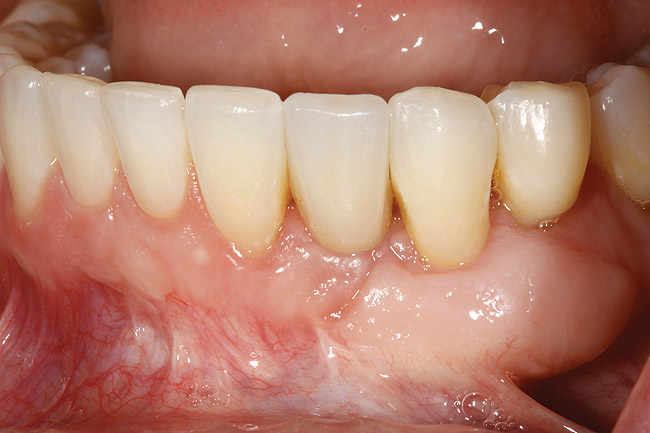

Figure 8  Adequate keratinized and attached gingiva after free gingival graft surgery.

Figure 8